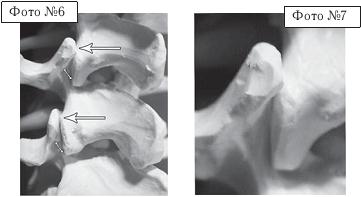

Фото № 3. На фото макета позвоночника стрелкой указан дугоотростчатый сустав позвоночника.

Дугоотростчатые суставы имеют синовиальную оболочку, фиброзную капсулу, суставную полость с синовиальной жидкостью, связки. Каждый дугоотростчатый сустав покрыт гиалиновым хрящом, по краю которого (на расстоянии 2–4 мм от края сочленяющихся поверхностей) прикрепляется капсула сустава. Изнутри суставная капсула покрыта синовиальной оболочкой. По передней поверхности она покрыта желтой связкой и составляет заднюю поверхность межпозвонкового отверстия. Капсула усиливается дорсально за счёт многораздельных мышц и вентрально жёлтой связкой, которая вплетается в неё в верхнемедиальном отделе. Верхний суставной отросток лежащего ниже позвонка массивнее нижнего и расположен больше кпереди и кнаружи, а нижний — кзади и кнутри. Часть верхнего суставного отростка у корня дуги участвует в формировании бокового углубления позвоночного канала.